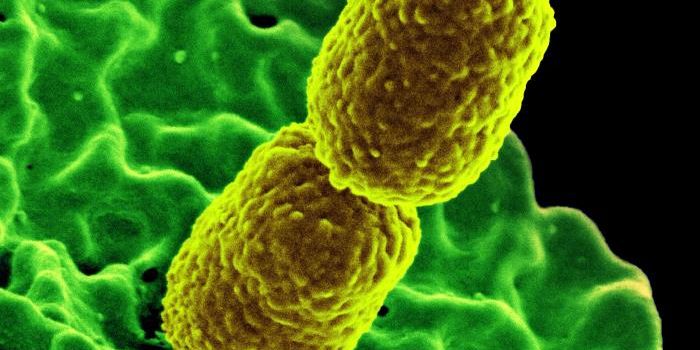

OCT 29, 2016Clinical & Molecular DXDespite frequent cleaning and sterilization, hospitals are notorious hotspots for germs and pathogens. And it’s no ...

MAR 10, 2021Clinical & Molecular DXMicrobiologists have discovered that the types of bacteria on a dermatitis patient’s skin affect the severity of t ...

AUG 07, 2022MicrobiologyPolio is a disease caused by the poliovirus. Polio can cause flu-like symptoms like nausea, headache, fever, and sore th ...

SEP 20, 2023Clinical & Molecular DXHospitals are supposed to help sick people get healthy, but unfortunately, many hospitalized patients become sick with i ...

MAR 19, 2017MicrobiologyIt can be incredibly challenging to give a patient the proper treatment when they are infected by an antibiotic-resistan ...

APR 13, 2022MicrobiologyApply the learnings of COVID to AMR, says coalition Tackling the deadly spectre of antimicrobial resistance (AMR) requir ...

AUG 16, 2020MicrobiologyBacteria in the gut have a powerful influence on our health, in part because all of those microbes have genes of their o ...

AUG 29, 2022MicrobiologyThe microbes in our bodies can have a significant influence on our health and well-being. While many studies investigati ...

OCT 18, 2019Health & MedicineMultidrug-resistant bacteria are frequently found in hospitals and long-term nursing facilities causing one of the large ...

AUG 23, 2022MicrobiologyWith effort, we all can help counter the rise of bacterial pathogens that resist the effects of multiple antibiotics.